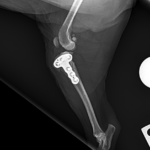

CBLO #205 超小型犬の前十字靭帯断裂に2.0 CBLOで対応しました。しばらく安静が必要です。 症例カテゴリー 放射線治療整形外科軟部組織外科脳神経外科内科腫瘍外科救急・集中治療リハビリテーション科腫瘍内科内視鏡科脳神経科呼吸器外科中医・漢方猫の腎移植循環器科